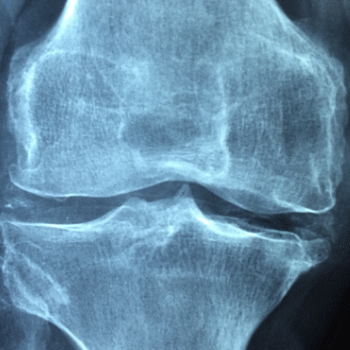

콘드로이친 효능 1. 관절 연골 보호 및 재생

콘드로이친은 관절의 연골을 보호하고 재생을 촉진하는 데 중요한 역할을 합니다. 연골은 관절에서 뼈와 뼈 사이를 부드럽게 움직이도록 돕는 쿠션 역할을 하는 조직입니다. 콘드로이친은 연골 세포를 보호하고, 외부 충격으로부터 연골을 보호하며, 세포외기질의 주요 성분으로서 연골의 구조와 기능을 유지합니다. 이를 통해 관절염 환자의 연골 손상을 줄이고, 새로운 연골 세포의 형성을 촉진하여 관절 건강을 개선합니다.